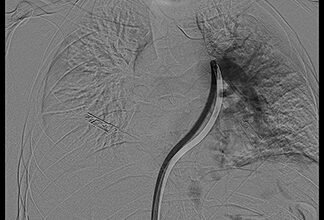

تقنية متقدمة تنقذ حياة مريض بمجمع الدمام الطبي

سجل مجمع الدمام الطبي أحد مكونات تجمع الشرقية الصحي ، إنجازاً طبياً نوعياً بعد نجاح فريق الأشعة التداخلية في إنقاذ…

في إنجاز طبي خلال العيد.. مجمع الدمام ينقذ مريضة من نزيف يهدد حياتها

في إنجاز طبي خلال العيد.. مجمع الدمام ينقذ مريضة من نزيف يهدد حياتها في إنجاز طبي يعكس الجاهزية العالية والكفاءة…